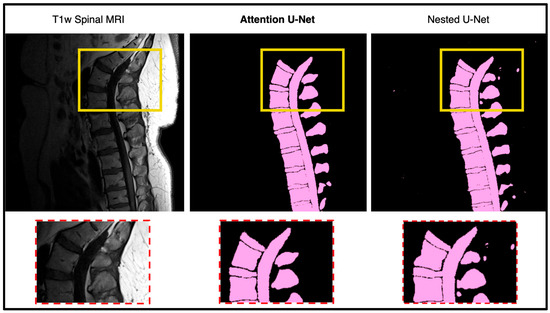

In this portion of the results, we focus on manually assessing the segmentation quality of the network outputs (Figure 5). While quantitative metrics like DICE and SSIM capture the quantitative performance of the segmentation models, we still wanted to see how these outputs are reflected in real time. DICE and SSIM might fail to highlight some subtle boundary mismatches or some issues in segmentation of complex structures. By incorporating qualitative observations, we aim to provide a more comprehensive evaluation of the network’s performance. Figure 6 shows the output of the model against the four other state-of-the-art U-Net networks. The attention U-Net is bolded as the top algorithm. Two algorithms that were close with respect to DICE, SSIM, and the radiologist reports were the Attention U-Net and the Nested U-Net. We thought it would be best if we showed the visualization to demonstrate the differences. Figure 7 highlights the difference and clearly shows the addition artifacts created by the Nested U-Net. While most of the segmentation is similar, the edges are not as clearly defined. The red boxes show the zoomed in portion of both, further demonstrating the difference between the two.

Figure 5. Qualitative comparison between Attention U-Net and Nested U-Net segmentation outputs on a lumbar T1-weighted spinal MRI. The highlighted regions show that Attention U-Net produces cleaner and more anatomically consistent boundaries, accurately following vertebral contours. In contrast, Nested U-Net introduces small artifacts and irregularities in adjacent soft tissue regions, indicating reduced boundary precision.